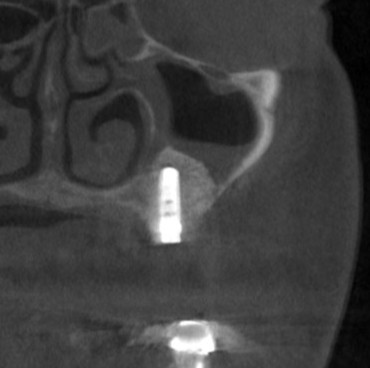

そこで、まず、2本目、3本目の部位に、サイナスリフトという上方の空洞に人工骨を填入する骨造成術を行いました(下の写真、3段目)。

後ろ2本の骨の高さは確保できましたので、インプラント埋入を行ないました。